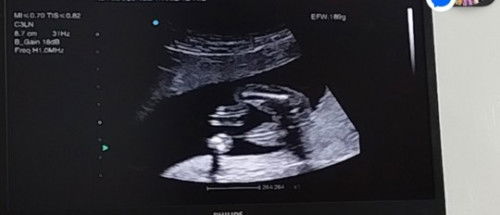

18 weeks na po kami ni baby ko, sa tingin nyo po baby girl or baby boy?

ung ob sono po ang makakpagsabi nya sau mommy nde po ntn mkkita s gnyn lng po